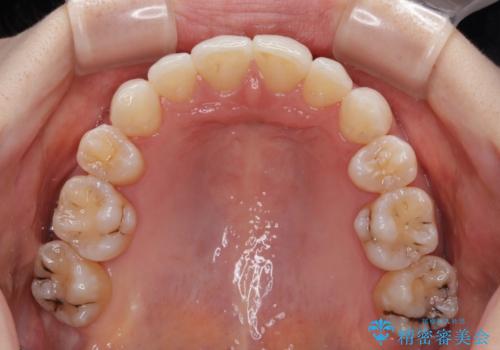

アンカースクリューを用いて正中位置を調整したことで、上下の正中位置をほぼ一致させることができました。

移動量が多かったため、治療期間は長くなりましたが、大変満足のいく仕上がりとなりました。